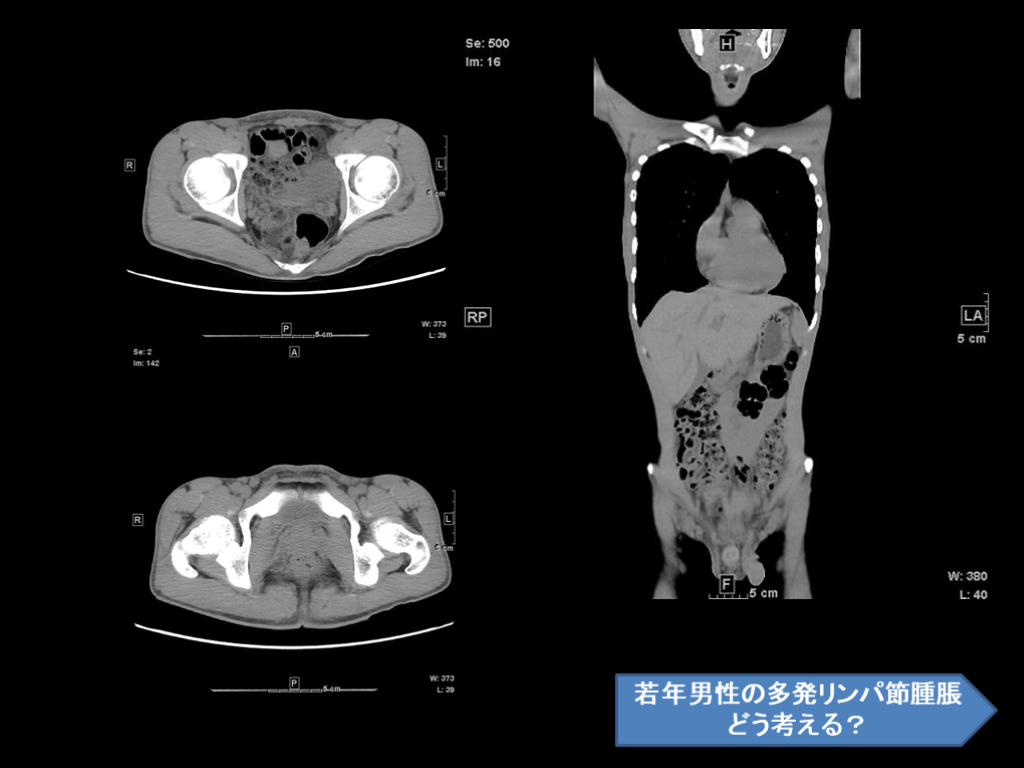

Question break20歳代前半 男性  【現病歴】 X月上旬、4㎝大の両側鼠径リンパ節腫脹に気が付き2週間ほど様子をみていた。しかし大きさに改善なく、前医を受診した際に頸部のリンパ節腫脹も指摘されたため同月24日に紹介受診。 発熱や盗汗などの全身症状、陰茎や睾丸の変形、腫脹、疼痛はないとのこと 今月上旬に一過性に鼻水が出ていた。熱、咳はなし 【既往歴】 アトピー性皮膚炎 【内服】 レボセチリジン5㎎ 以前から内服 【アレルギー】 抗生剤でアナフィラキシー 【生活】 一人暮らしの学生   喫煙なし      sexual contactなし 動物接触なし 海外渡航なし

Vital sign 特記事項なし 右頸部  2㎝大のリンパ節触知 圧痛なし、可動性良好 右鎖骨上 2㎝程のリンパ節腫脹 滑車上リンパ節 触知せず そけい部      扁平で軟らかい4㎝超えるリンパ節を数個縦方向に触知    圧痛なし、可動性良好 (アトピー皮膚炎) 全身苔癬化伴い発赤++  掻痒感強く掻爬痕多数

WBC 8500  NEUT% H 75.4  LYMPH% L 9.0  MONO% 6.7  EO% H 7.6  BASO% 1.3 RBC 477 Hb 14.1 MCV 89 PLT 30.9 CRP   0.07 TP 7.3 T.BiL 0.4 AST 22 ALT 9 ALP 75 LDH P 564 γ-GTP 11 AMY 53 T-Chol 136 TG 55 BUN 14.6 CRE 0.72 UA 5.1 Na 138 K 3.7 Cl 105 Ca 9.1 血糖 88 ALB 4.0

フェリチン  37 IgG H 1783 IgA 182 IgM 68 IgG4 H 322.0 HIV-1/2抗体 0.1 IL2レセプター   H 822 抗核抗体 <40

若年男性の多発リンパ節腫脹 どう考える?

「全身性で大きく圧痛もない」生検してもよいリンパ節の性状だが‥患者さんと相談し生検はpendingアトピー性皮膚炎の治療を強化さらにデュピルマブ(IL4/13受容体抗体)開始皮膚所見の改善とともにリンパ節縮小 診断は?

皮膚病性リンパ節腫脹Dermatopathic lymphadenopathy (慢性)皮膚疾患からリンパ節腫脹をきたす アトピー性皮膚炎 悪性腫瘍(菌状息肉症, Sezary, HTLV)でも